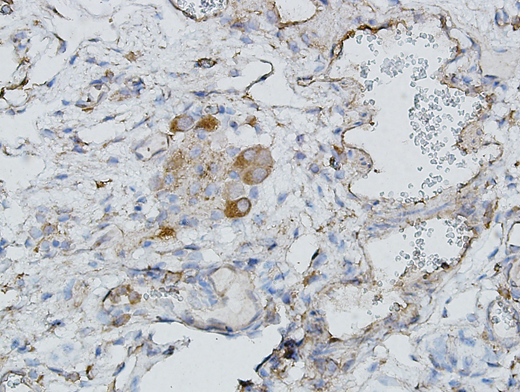

Using tissues obtained from thirteen horses euthanized for non-thrombotic conditions, immunohistochemical stains indicate the presence of ADAMTS13 in equine liver and colon. Furthermore, in one horse with colic, immunohistochemical staining of the resected colon indicates the presence of ADAMTS13 in the aboral margin (Figure 1) and the absence ADAMTS13 staining in the diseased tissue.